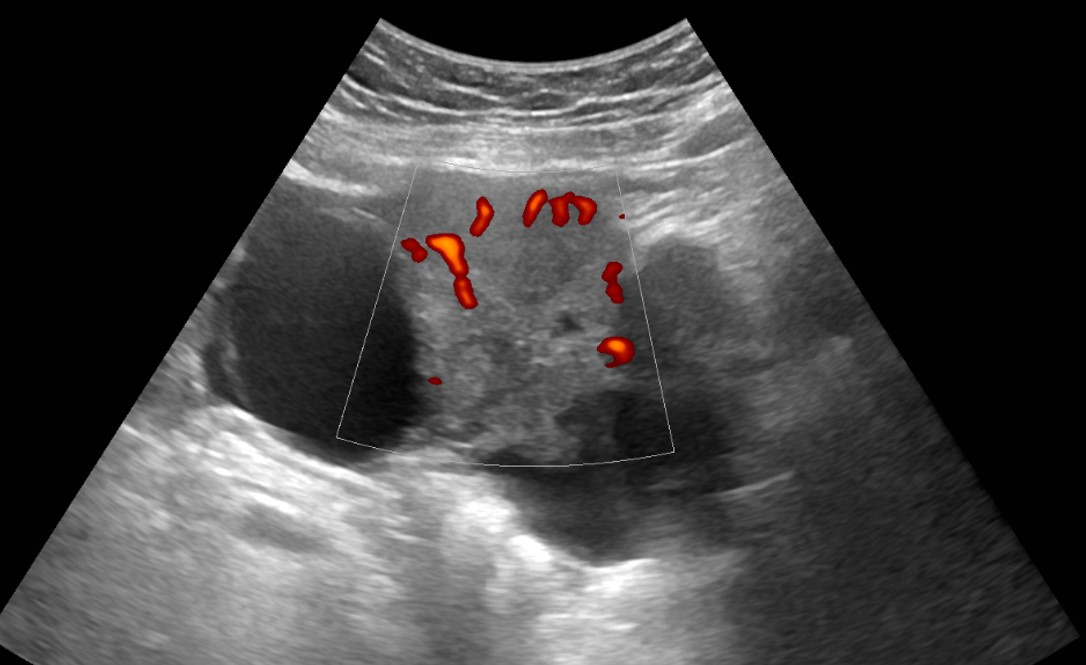

mioma_parido_gel

Ultrassonografia transvaginal com Doppler colorido. Observa-se formação sólida intracavitária, heterogênea, com pedículo vascular identificado ao Doppler, exteriorizando-se através do canal cervical. Achados compatíveis com mioma submucoso pediculado em processo de exteriorização (mioma parido).